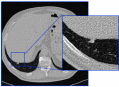

Pleural Nodule Detection in Chest CT

A CAD

has been developed for the automatic detection of pleural nodules in

pulmonary CT images. The project was part of the INFN experiments

called MAGIC5 (Medical Applications on a Grid Infrastructure

Connection) and M5L (MAGIC5 Lung).